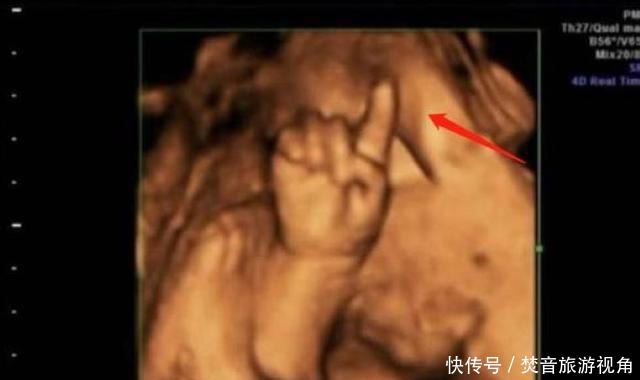

第一次做检查时,胎儿的脸部、身体都看得非常的清楚,让陈女士感到了很大的安慰。值得一提的是,孩子的一只手伸出了一个手指,非常的可爱。让人没想到的是,第二次检查时,孩子的手指伸出了两根,第三次手指变为了三根,最后一次检查,孩子的手指就变成了四根。

医生看到这种情况,也是非常的吃惊,他还调侃道:这孩子可是北大清华的料,可不能耽误人家,陈女士听后非常的开心。就这样,"天才胎儿"在网上迅速火了起来,他在子宫中掰手指算数成为了网友们新奇的谈资。